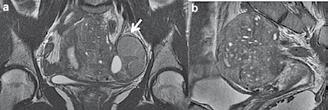

Imagine 4. IRM pelvin

Rezonanța magnetică nucleară (RMN)

Deși EEV este prima opțiune de imagistică în diagnosticarea adenomiozei, RMN poate contribui cu informații utile și crește performanța de diagnostic în cazurile dificile, spre exemplu în cazul coexistenței altor leziuni de tipul fibroamelor.

Apariția RMN-ului a revoluționat imagistica pelviană la femei. Tehnica este cea mai fiabilă modalitate imagistică pentru evaluarea patologiei uterine. Este mai puțin dependentă de operator și poate oferi imagini standard și reproductibile de la o examinare la alta. RMN poate defini atât anatomia internă normală a uterului, cât și monitoriza diverse schimbări fiziologice. Numeroase studii au descris datele RMN și au evaluat capacitatea de diagnostic a RMN-ului în evaluarea pacien-

telor cu adenomioză, precum și secvențele optime utile unei astfel de evaluări.

Imaginile care sugerează invazia endometrială și neregularitățile din zona joncțională, ob-servate la RMN, sunt utilizate în mod obișnuit pentru diagnosticarea adenomiozei, dar sunt preferabile criteriile obiective. S-au identificat trei parametri obiectivi pentru diagnosticul RMN al adenomiozei:

1. îngroșarea ZJ de cel puțin 8-12 mm; 2. raportul grosime maximă a ZJ/grosimea totală a miometrului peste 40% și

3. diferența dintre grosimea maximă și cea minimă din zona joncțiunii (JZmax-JZmin = JZ dif) mai mare de 5mm.

Deși primele două criterii au fost criticate din cauza modificării grosimii ZJ in funcție de starea hormonală și a ciclului menstrual, a treia pare a fi mai independentă de starea hormonală, fiind o diferență de două măsurători luate în aceeași fază hormonală (6) .

Imagistica prin RMN este o modalitate precisă, neinvazivă pentru diagnosticarea ade-nomi- ozei cu o specificitate (85% -95%) și o sensibilitate ridicată (67% -99%).

RMN la un caz cu adenomioză. Imagini T2

- (a) plan coronal și (b) plan sagital.

Focarele de adenomioză apar evident ca zone rău delimitate și cu semnal acăzut. Chisturile apar ca zone hiperecogene care corespund cu endometrul ectopic. În zona anexei stângi se observă hidrosalpinx (săgeata albă).